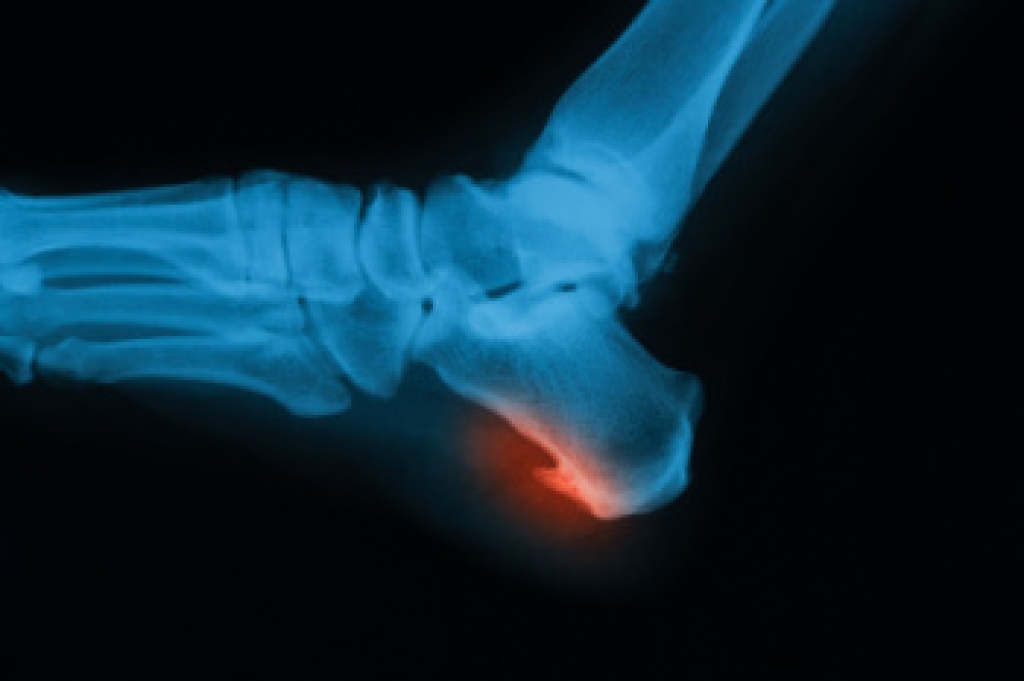

The feet contain 26 bones each, creating numerous joints and surfaces where bone spurs may develop from repeated stress, inflammation, or injury. These bony growths, known as osteophytes, often form when the body responds to pressure or friction. If conservative care does not ease symptoms, a podiatrist may suggest surgery to remove the bone spur or address any tight tissues that may be contributing to discomfort. Resection surgery trims away the excess bone, and the type depends on the location. A dorsal spur excision is on the top of the foot, an inferior heel spur resection is under the heel, and a posterior heel spur removal is at the back of the heel. If soft tissue is involved, plantar fascia release or partial Achilles tendon release may be employed. In cases of severe joint damage, joint fusion can stabilize the area while joint replacement can restore movement. If you are experiencing this type of foot pain, it is suggested that you schedule an appointment with a podiatrist for an exam and appropriate treatment options.

- Removing foot deformities like bunions and bone spurs